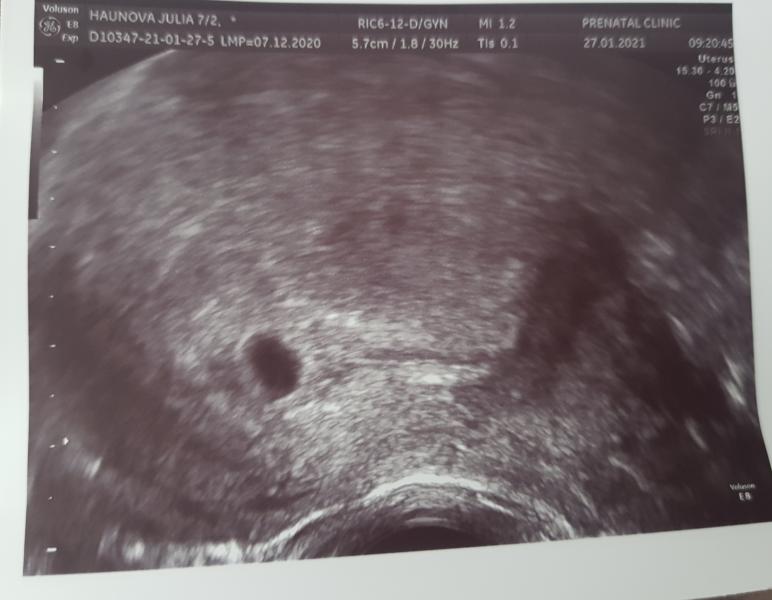

Плодное яйцо растет,2 недели назад было 2,7 ,сейчас 6,8 что соответствует сроку 5 недель!!! А по М. у меня уже 7 недель... сказали,что возможно была поздняя овуляция...

У меня по месячные срок должен был быть 7-8недель,а по УЗИ 5-6недель.Просто была поздняя овуляция.